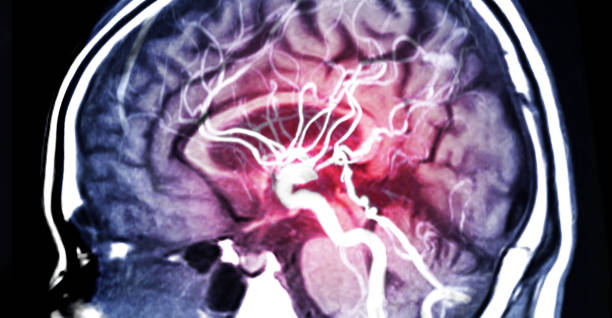

모야모야병은 중추신경계 질환 중 하나로, 이상한 소리와 자세, 신체적인 증상 등을 일으키는 질환입니다. 이 병은 실제로는 정신의학적인 질환으로 분류되며, 정확한 원인은 아직 알려지지 않았습니다. 하지만, 뇌의 신경전달물질인 도파민과 관련이 있을 수 있다는 가설이 제기되고 있습니다.

모야모야병의 특징은, 갑작스럽게 발생하는 이상한 소리와 자세, 그리고 다양한 신체적인 증상 등입니다. 환자는 자발적으로 특이한 소리나 움직임을 발생시키는 것이 아니라, 이것이 강제적으로 발생되기 때문에 어쩔 수 없이 소리를 내거나 움직임을 하게 됩니다. 이로 인해 일상생활에 큰 어려움을 겪을 수 있으며, 사회적인 이슈가 될 수도 있어 조기에 진단 후 치료를 받으셔야 합니다. 따라서 이번 시간에는 발생률이 높아지고 있는 모야모야병 증상에 대해 자세히 알아보겠습니다.